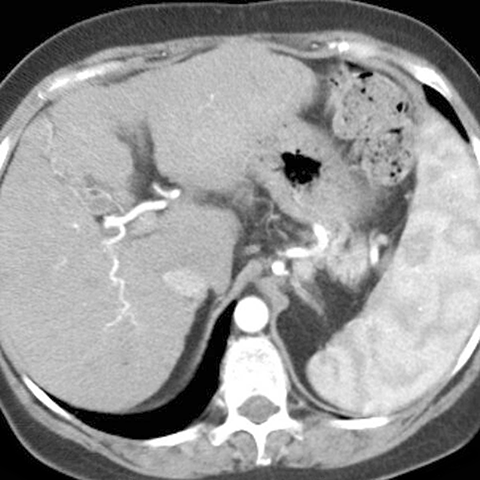

Heterogeneous Splenic Enhancement [1 of 2]